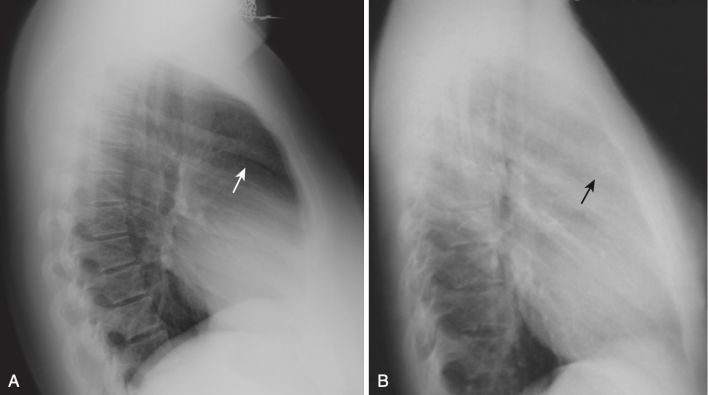

Các rãnh liên thuỳ

- Trên phim nghiêng, có thể nhìn thấy cả rãnh lớn (chéo) và bé (ngang) dưới dạng các đường nhỏ, màu trắng (dày khoảng bằng đường kẻ bằng đầu bút chì). Các rãnh phân định các thùy trên và dưới ở bên trái và các thùy trên, giữa và dưới ở bên phải.

- Các rãnh lớn chạy theo hướng chéo, khoảng từ mức của đốt sống ngực thứ 5 đến một điểm trên bề mặt cơ hoành của màng phổi sau xương ức vài cm. Rãnh bé nằm ngang mức xương sườn thứ 4 trước (chỉ có ở bên phải) và hướng theo chiều ngang (xem Hình 3).

- Có thể nhìn thấy cả rãnh lớn và rãnh bé trên phim nghiêng, nhưng do mặt phẳng chéo của rãnh lớn nên thường chỉ có thể nhìn thấy rãnh bé trên phim thẳng.

- Khi một rãnh chứa chất dịch hoặc bị xơ hóa do một quá trình mãn tính, rãnh sẽ dày lên (Hình 8). Rãnh dày lên do dịch hầu như luôn kèm theo các dấu hiệu khác của dịch trong lồng ngực, chẳng hạn như các đường Kerley B và tràn dịch màng phổi. Rãnh dày lên do xơ hóa là nguyên nhân có nhiều khả năng hơn nếu không có các dấu hiệu khác của chất dịch trong ngực.